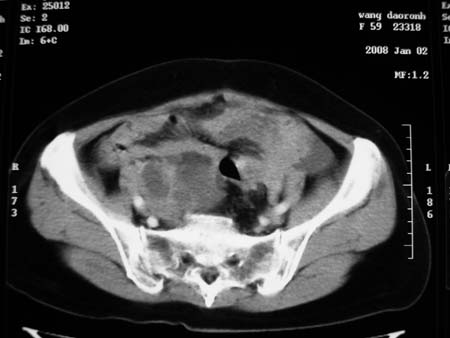

以下是引用卜一在2008-1-2 20:39:00的发言:[br]右侧附件区囊实性肿块,与膀胱壁分界不清,增强后实性部分显示强化。考虑为:右侧卵巢囊腺癌可能性大。支持!

以下是引用zhengfaming在2008-1-2 19:28:00的发言:[br]右下腹腔内附件区可见一囊实性混合密度块影,先考虑囊腺癌